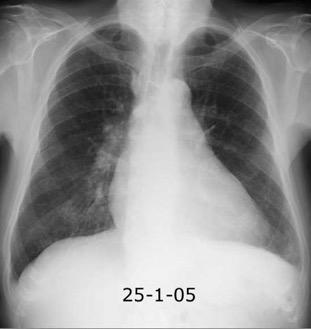

Síndrome de afectación postcardiaca (postcardiac injury)

Post infarto 1-7 % (Dressler)

Trauma cerrado Implantación marcapasos

Cirugía cardiaca. 17-31% (Post.pericardiotomía)

3707 pacientes 29 Derrames (0,78%) > de 25% del hemitórax

Todas menos 2 Izdos.

Angioplastia

By-pass coronario 21-10-03